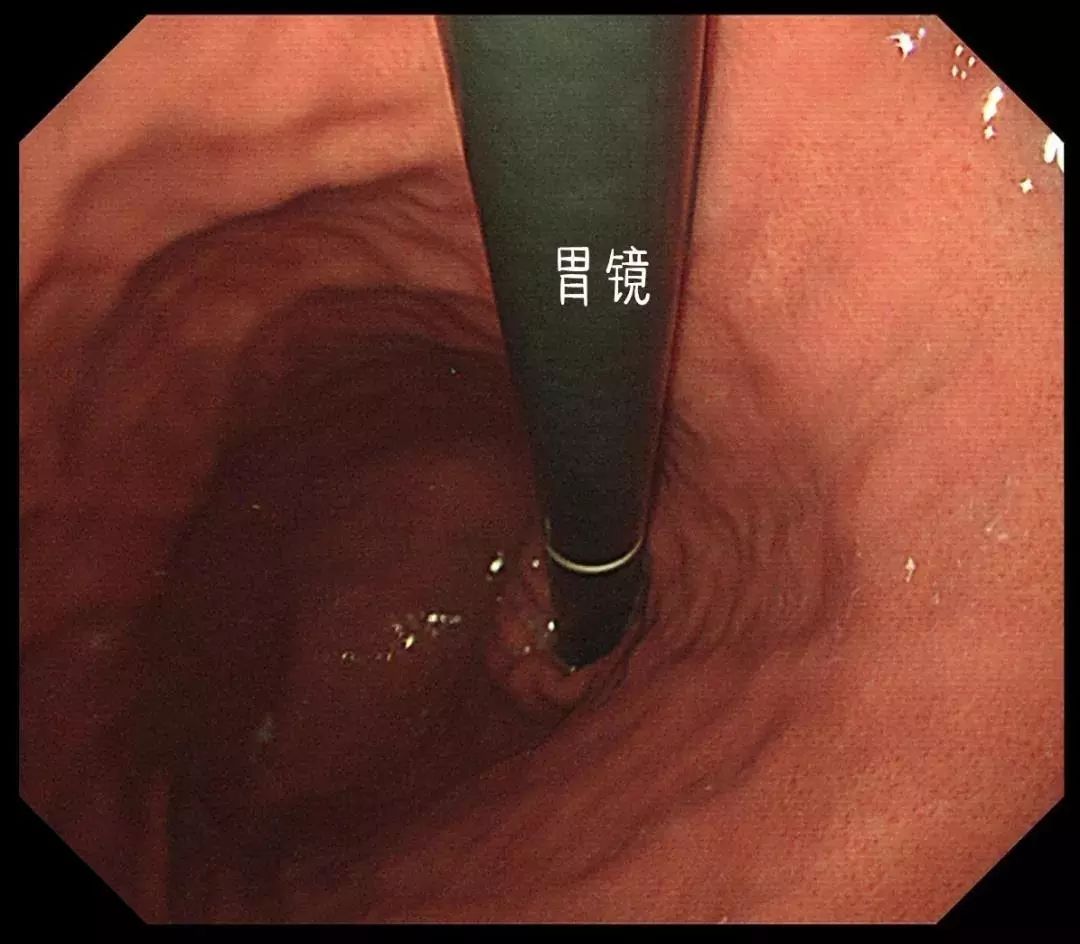

准备的较好的胃镜下图像

经过一整晚的禁食,胃部的食物已经排空。在第二天早上,因为还没进食,胃中也不会分泌过多的胃酸,所以可以看到比较清晰的“景象”。